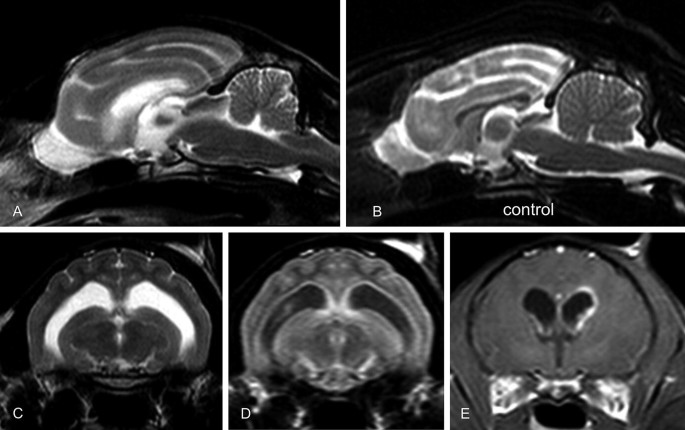

Hydrocephalus In Animals Springerlink